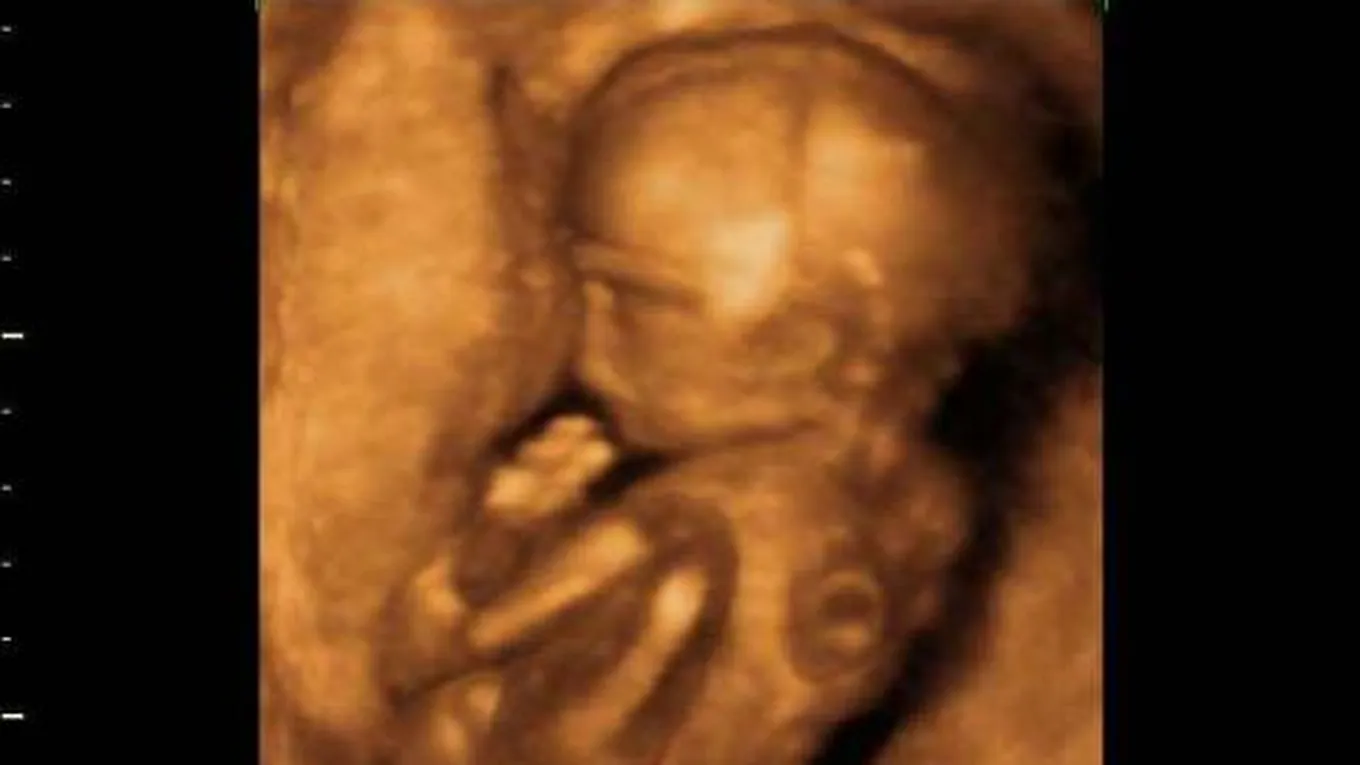

أعراض الأسبوع الخامس من الحمل

إنّ جميع التغييرات التي تظهر على المرأة خلال أشهر حملها تكون بهدف مساعدة الجنين على النمو والتطور بشكل طبيعي، وخلال الأسبوع الخامس من الحمل تطرأ على الحامل مجموعة أعراض وتغيّرات ومن أبرزها ما يلي: